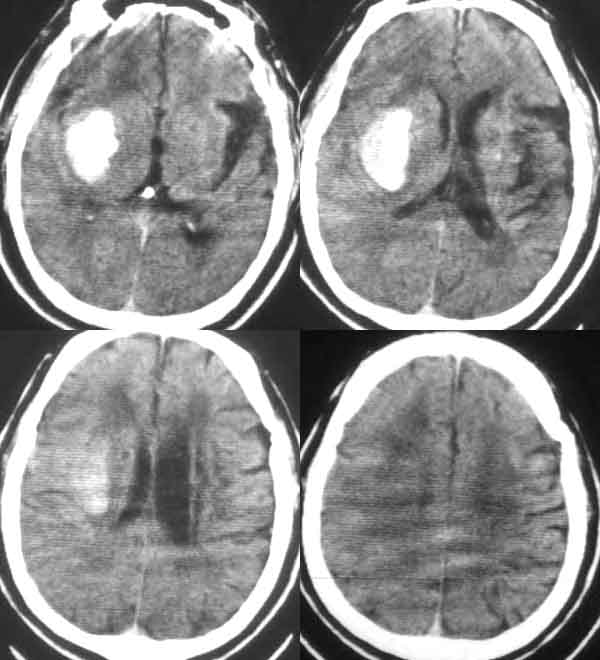

男53岁,既往有腔梗病史。突然昏迷。是多发脑出血吗?都是什么位置的?

右侧基底节区出血,双侧基底节区腔隙性脑梗塞,左侧基底节区脑软化灶。

右基底节区脑出血  双基底节区脑腔隙

右侧基底节区出血,双侧基底节区腔隙性脑梗塞.

右侧基底节区出血,双侧基底节区腔隙性脑梗塞伴脑萎缩.

典型的右侧颞叶、基底节区原发性脑出血。

右侧基底节区出血,双侧基底节区腔隙性脑梗塞伴脑萎缩

右侧颞叶、基底节区原发性脑出血;腔隙性脑梗塞;局限性脑萎缩。

1. 右侧基底节区出血,双侧基底节区腔隙性脑梗塞伴脑萎缩。

右外囊血肿;双基底节腔梗;皮脑;脑萎缩

右侧颞叶、基底节区原发性脑出血。